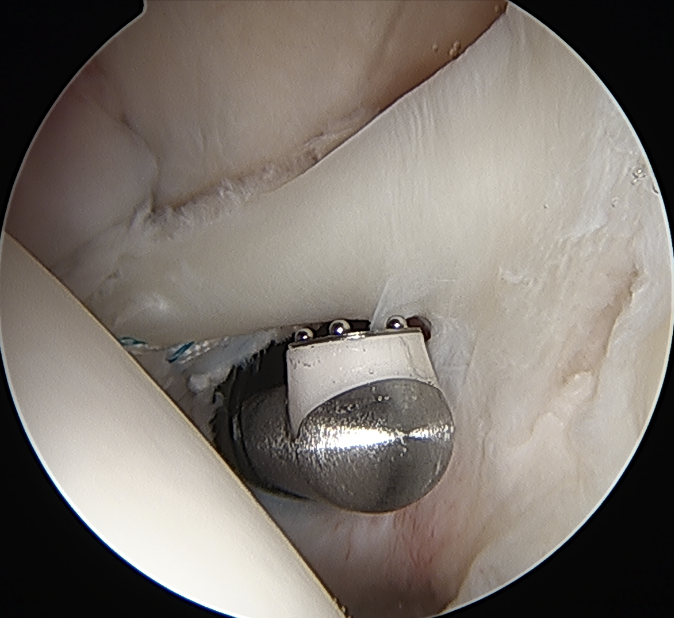

Anchor biceps tendon into bicipital groove

Bicortical open subpectoral biceps tenodesis using Arthrex Biceps Button